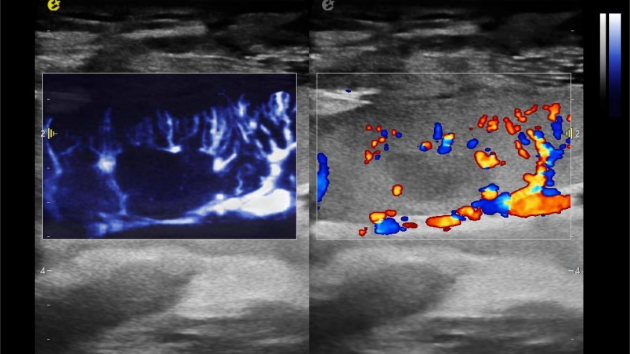

2) 可检测20-50μm级细小血管低速血流信号,能看清头发丝1/2粗细的微血管;

3) 通过血管指数(VI)定量评估局部血管密度,以定量化数据实时监测血流灌注情况,预判肾功能恢复情况;

肾脏的灌注评估,RI/VI量化数据

超微视血流显像评估肾移植术后灌注情况

这一项无创、无辐射操作简便且无需造影剂的黑科技,相当于用"高速摄像机"记录血液细胞的运动轨迹,让血管并发症"无处遁形。